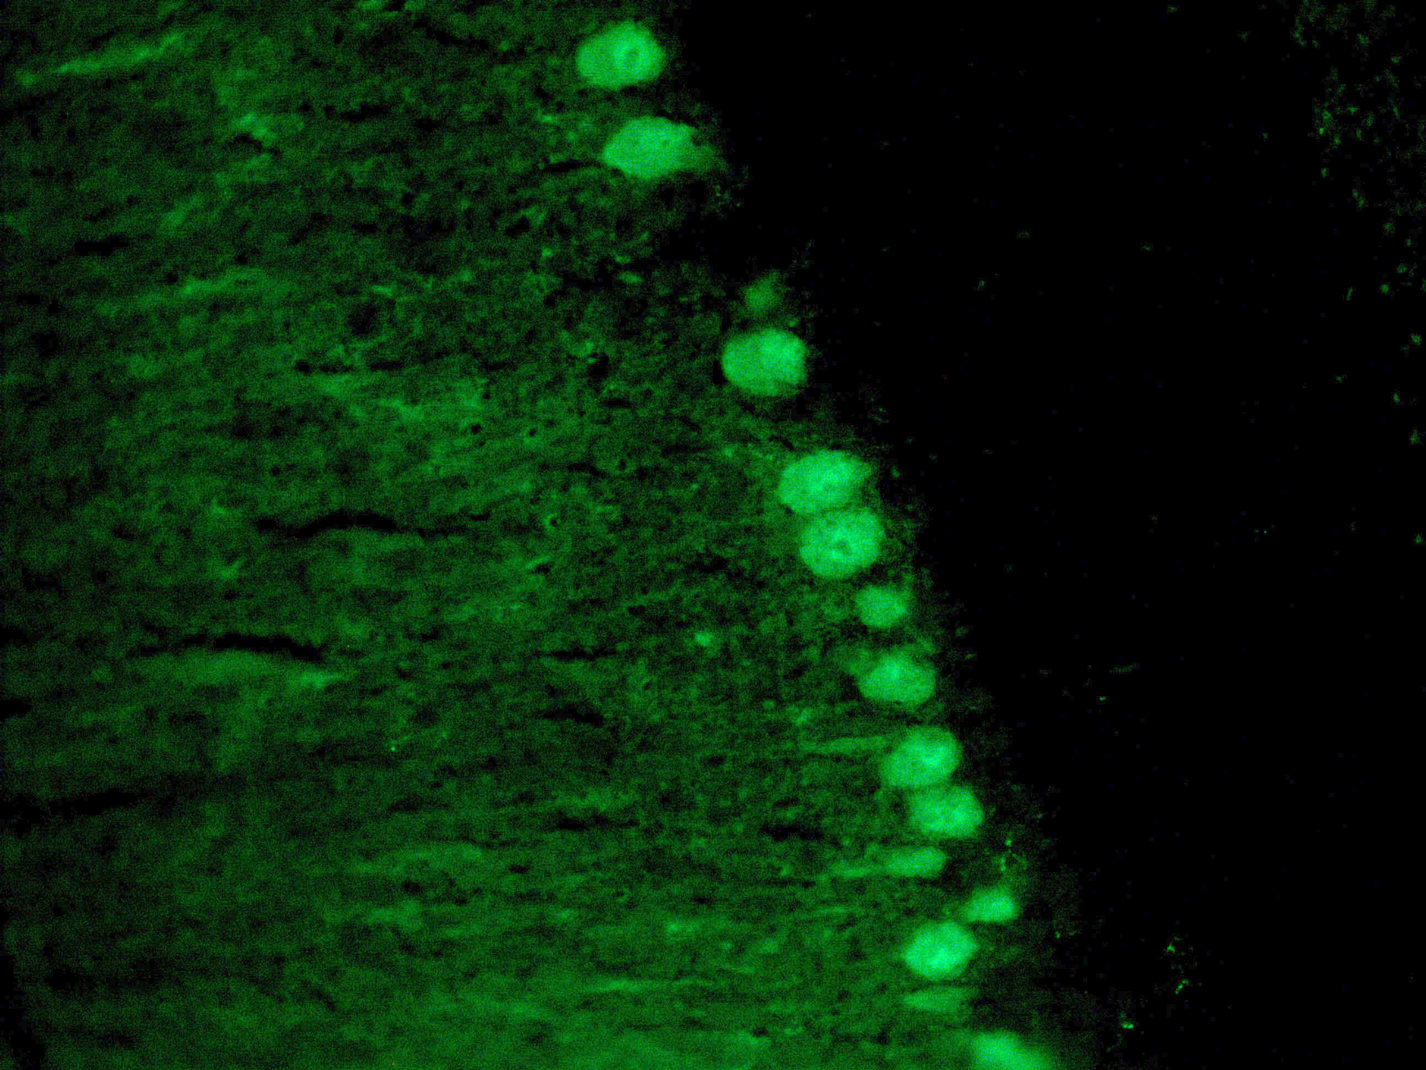

Credit photo: Cellule di Purkinje nel cervelletto murino

Reazione immunoistochimica con anticorpo anti-calbindina che evidenzia le cellule di Purkinje nel cervelletto di un modello murino di atassia spinocerebellare di tipo 1 (SCA1).

Ingrandimento 400×.

Purkinje cell COX deficiency and mtDNA depletion in an animal model of spinocerebellar ataxia type 1. Ripolone M, Lucchini V, Ronchi D, Fagiolari G, Bordoni A, Fortunato F, Mondello S, Bonato S, Meregalli M, Torrente Y, Corti S, Comi GP, Moggio M, Sciacco M.J Neurosci Res. 2018 Sep;96(9):1576-1585. doi: 10.1002/jnr.24263.PMID: 30113722.